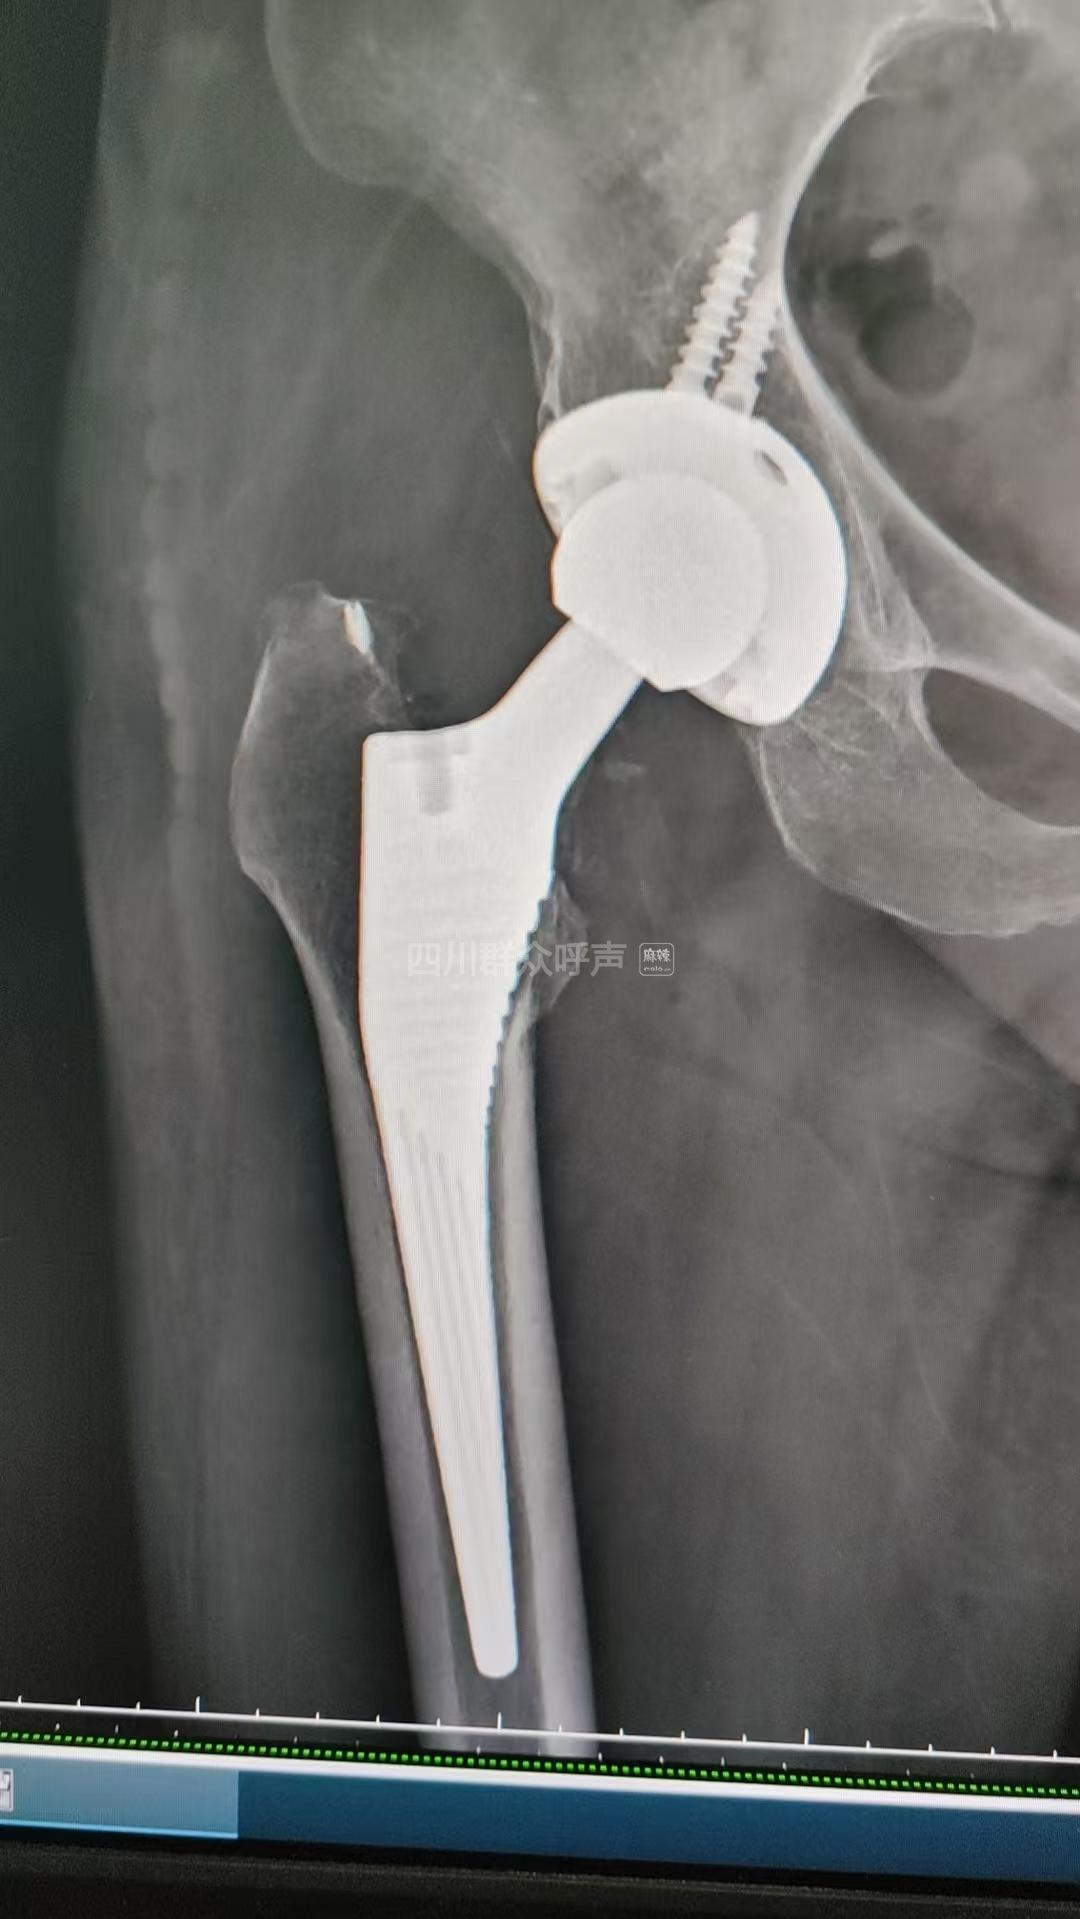

[咨询] 老人意外摔伤造成髋关节骨折